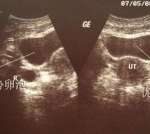

另外,通过B超检查还能够了解胎儿的实际情况,比如胎儿是多胎还是一胎,是否存在子宫内,有没有发生宫外孕等情况,如果是宫外孕的话也能及时进行处理,而且还能通过B超来知道孕妇的羊水是否充足,胎心是否正常等。

羊水深度是指的是通过B超检查羊水池的垂直深度,是判断羊水多少的一个重要指标,正常范围在2-8cm,如果小于2cm表示羊水过少,大于8cm表示羊水过多,羊水过多的话,胎儿有畸形的可能,羊水过少就容易导致儿临产期造成胎粪淤积,甚至出现早产或窒息。